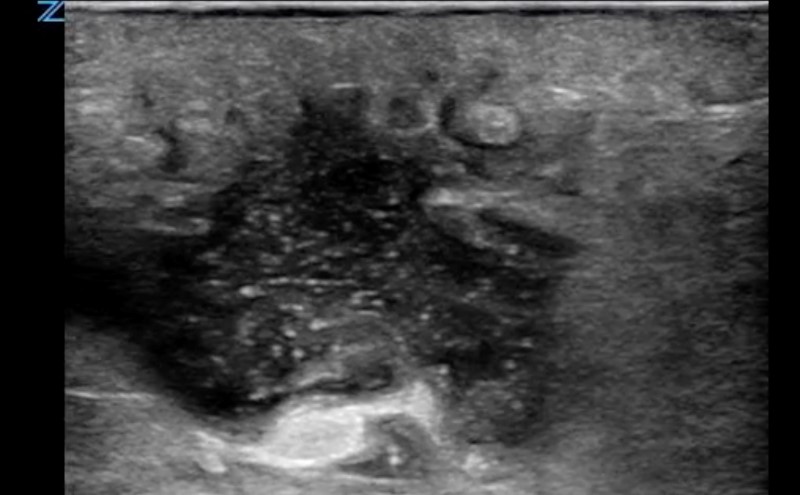

- On ultrasound, an abscess is a spherical or oblong structure that is largely anechoic or hypoechoic.

- Figure 2. Abscess containing hyperechoic debris

- However, as opposed to a simple cyst that will be uniformly anechoic throughout, an abscess will contain hyperechoic debris. This feature can be used to differentiate an abscess from a cyst.

- The walls of the abscess cavity might be distinct and hyperechoic, or they might have a ragged appearance and intermix with the adjacent tissue. Because of the anechoic nature of the abscess, posterior acoustic enhancement might be seen.

- On ultrasound imaging, an abscess appears as a spherical or oblong anechoic or hypoechoic collection containing hyperechoic debris.